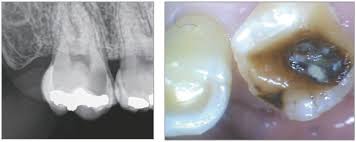

- X‑ray 및 육안 진단 → 상태 확인

씹을 때 통증, 푹 꺼지는 느낌 등이 느껴진다면 크라운 손상 가능성을 의심해야 합니다. 특히 신경치료한 치아가 노출되었다면 즉시 치과를 방문해야 합니다.